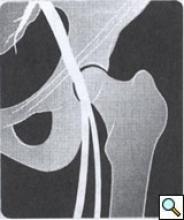

| Figure 1: Access below the inguinal ligament. |

Most right handed physicians will prefer the patient’s right groin for femoral access, although both groins should be prepped in case of inaccessibility. After the pulse is identified, the inguinal ligament is found by tracing a line between the anterior iliac spine and the pubic tubercle. Often, especially in obese individuals, the inguinal crease is inferior to this landmark. Access should be made below the inguinal ligament corresponding to the common femoral artery (Figure 1). One will find that if access is made too high, corresponding with the external iliac artery, hemostasis is difficult to achieve with manual pressure. In this case hemorrhage can occur after removal of devices and a retroperitoneal hematoma can develop. This is often insidious in onset. In addition, the risk of pseudoaneurysm formation is higher in an external iliac stick, again because direct manual pressure cannot be applied this superiorly.